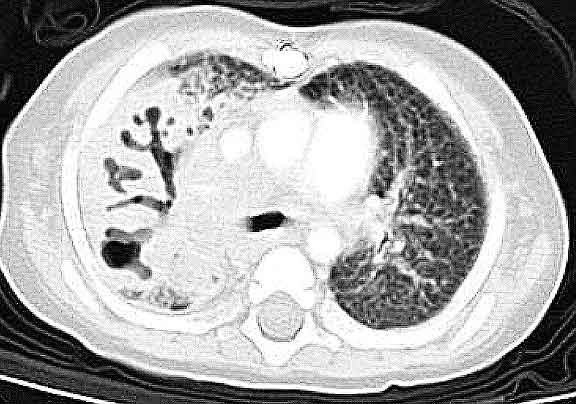

Below are CHEST CT results.

Enlarge

this CHEST CT.

Enlarge this CHEST CT.

WHAT

IS YOUR INTERPRETATION FOR THE CHEST CT?